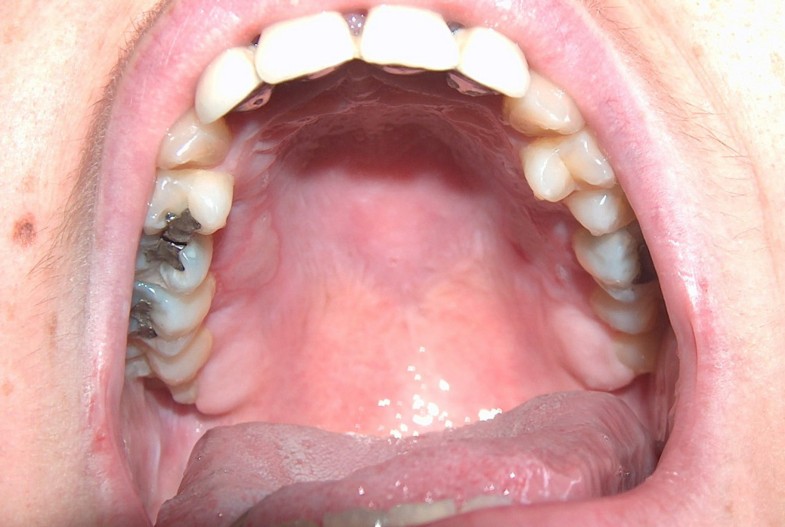

from smartmouth.com

Sore Roof of Mouth Causes & Treatment SmartMouth